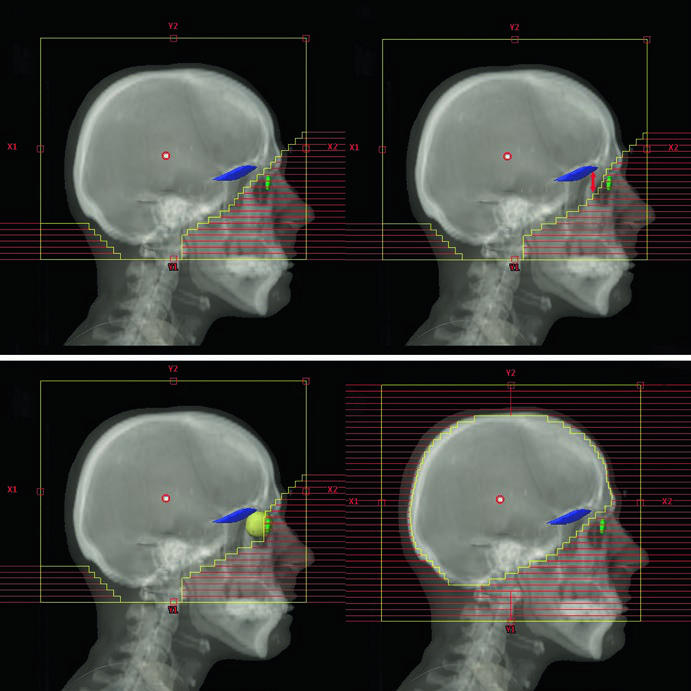

O planejamento muda conforme o cenário clínico. Metástases difusas (numerosas ou “incontáveis”) e PCI para SCLC recebem campos convencionais. Doença leptomeníngea exige cobertura adicional dos nervos ópticos, região retroorbital e lâmina cribosa, com margens expandidas de 8–10 mm para penumbra e setup diário nos lobos temporais e placa cribiforme. A leucemia e o linfoma de SNC demandam inclusão da retina e, se houver envolvimento ocular confirmado por exame de lâmpada de fenda, cobertura dos globos oculares inteiros.

| Doença Leptomeníngea | 3D-CRT lateral oposta | Conteúdo craniano + nervos ópticos + região retroorbital + lâmina cribosa | Lobos temporais e placa cribiforme com margem adicional de 8–10 mm para penumbra e setup |

| Linfoma/Leucemia de SNC | 3D-CRT lateral oposta | Conteúdo craniano + nervos ópticos + região retroorbital + retina ± globos inteiros | Posterior 1/3 dos globos se sem envolvimento ocular; globos inteiros se envolvimento confirmado |

| Scalp-Sparing | 3D-CRT lateral oposta | Conteúdo craniano inteiro | Borda do MLC posicionada na tábua externa da calvária |

| HA-WBRT | IMRT/VMAT | CTV: parênquima cerebral até o forame magno; PTV: CTV menos (hipocampos + 5 mm) | Sem margem de setup adicional |